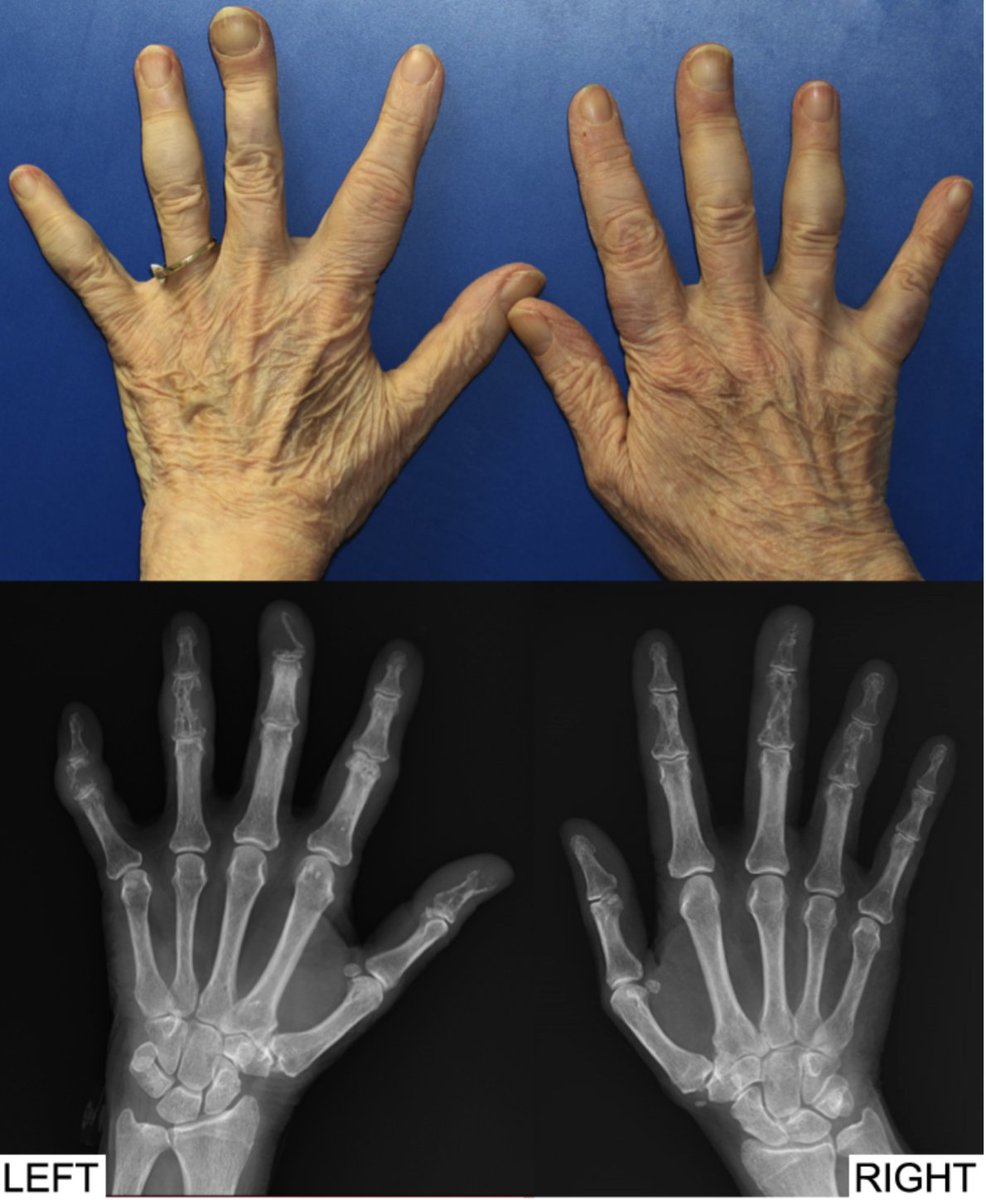

Clinical Images from Arthritis & Rheumatology: Sarcoid dactylitis Full article: https://doi.org/10.1002/art.41212 … View on Instagram: https://www.instagram.com/p/B8Bz8k2gNT-/ pic.twitter.com/s3q38UbrG0